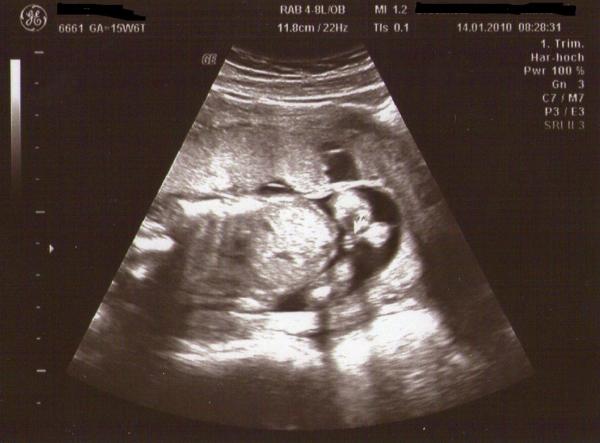

Hallo,habe ein Ultraschallbild und würde gerne mal andere Meinungen hören was das Geschlecht betrifft! Wer sieht denn was? Da wo der weiße Pfeil drauf zeigt!

3 Striche... eindeutig Mädchen

Laut Arzt auf dem Bild eindeutig Mädchen, aber waren vor ein paar Tagen nochmal da, da wollte er keine Prognose abgeben. Das wichtigste ist ja das, das Baby gesund und wir freuen uns auch wieder über einen Jungen... Ist nur die neugier, vielleicht hat ja hier jemand schon ein ähnliches Bild gehabt

das ist ein mädchen. 3 punkte ist ein mädel. lg cassi juli 09 mama